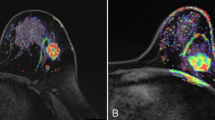

Magnetic resonance imaging (MRI) equipment used was a Philips Achieva 1.5 T MRI scanner with a dedicated bilateral breast coil. Patients were placed in the prone position, and both breasts were naturally suspended inside the hole in the center of the coil, without compression. The patients were asked to breathe softly and remain motionless. A venous channel was established in advance in the upper arm of each patient, and a long indwelling catheter with a three-way junction was implanted. The two other ends of the three-way junction were connected to 20 ml normal saline and 0.1 mmol/L/Kg dose of contrast agent gadodiamide injection. At the same time, a dynamic scanning sequence was set, and the scanning range covered the entire breast. Six DCE-MRI scans were performed, each lasting for 90 s. First, the masking film was scanned (the first scan). The patient was asked to remain in the original position, and the interval between each scan was 30 s. After the scanning was suspended, a bolus of contrast agent (injected at a speed of 2.5 ml/s, and then 20 ml bolus of normal saline) was injected using a high-pressure syringe. After the suspension was concluded, the scans were performed five times consecutively. The duration of each 3D dynamic sequence scan was 90 s, and the total duration of dynamic enhancement was 9 min. The maximum diameter line and three-dimensional volume of the tumor body were measured using DCE-MRI and magnetic resonance diffusion-weighted imaging (DWI), respectively, and reflected the size and volume of the lesion. On DCE-MRI, the region of the tumor with obvious enhancement (avoiding the necrotic area) was selected as the region of interest, and a time–intensity curve (TIC) was drawn. TIC is an indicator reflecting the microvascular density and vascular permeability of the tissue, and is divided into three types: type I is the inflow type, that is during the dynamic acquisition time, the signal curve shows a continuous and slow increase; type II is the platform type, that is during the dynamic acquisition time, the signal curve begins to rise significantly, and then remains flat; and type III is the outflow type, that is during the dynamic acquisition time, the signal curve begins to rise significantly, and then decreases significantly. DWI was used to analyze the tissue structure and internal characteristics based on the diffusion of water molecules in tissue cells. This method not only provides morphological information of the tumor but also helps evaluate the efficacy by measuring the apparent diffusion coefficient (ADC) of the tumor before and after chemotherapy.

In this paper, we only discuss imaging evaluation methods, wherein, MRI mainly reflects the efficacy of NAT in breast cancer based on the characteristics of lesion morphology and size, dynamic contrast-enhanced semi-quantitative or quantitative parameters, ADC values, and magnetic resonance spectroscopy (MRS) [16,17,18]. In addition, due to the tumor cell death and reduced cell density, breast cancer patients who are in remission after NAT also present with reduced DWI signals and increased ADC values [19]. At present, multi-parametric MRI (mpMRI) imaging omics lack unified criteria for the selection of different sequence omics, which limits its technical promotion [20, 21]. The traditional mono-exponential model diffusion-weighted imaging (mono-exponential-DWI) is an imaging method for calculating the voluntary movement of water molecules in the tissue gap using a single exponential function. ADC is the most commonly used clinical parameter, reflecting the degree of tissue limitation. The pathological mechanism of applying ADC values to breast tumors is that the proliferation of tumor cells leads to an increase in cell numbers, disorder of tissue structure, and reduction of extracellular space, resulting in the limitation of water molecule movement in the intercellular space of the tissue, increase in DWI signals, and decrease in ADC values. Therefore, there was a significant correlation between ADC values and cell density. At present, however, the correlation between different molecular subtypes and ADC values remains unclear. However, according to several studies, the ADC values of different molecular subtypes are different [22,23,24,25,26,27], and there is no consensus on the best b value of breast DWI. This study further verified the predictive effect of enhanced MRI findings on the outcomes of neoadjuvant therapy. In this study, we found that the therapeutic effect of neoadjuvant therapy can be better evaluated by combining clinical physical examination, color ultrasound, and nuclear magnetic resonance evaluation. The three methods complement each other to avoid the insufficient evaluation of a single method, which is convenient for the majority of prefecty-level hospitals to carry out. In addition, the method is simple and feasible and suitable for promotion.